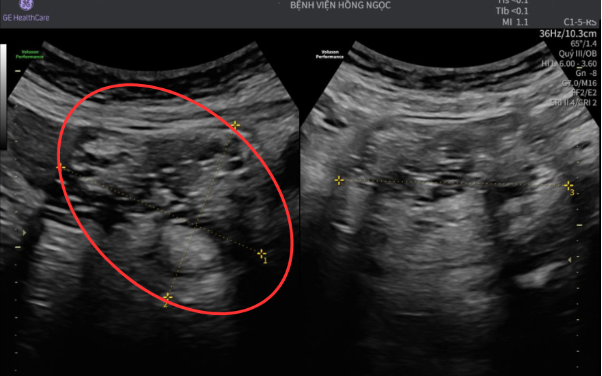

Tại đây, chị được chỉ định siêu âm, kết quả cho thấy hình ảnh hỗn hợp âm gồm tổ chức đặc và dịch kích thước hơn 7cm, nghi ngờ u bì buồng trứng, hay còn gọi là u quái trưởng thành. Đây là một loại u lành tính có nguồn gốc từ tế bào mầm, loại tế bào có khả năng phát triển thành nhiều mô khác nhau như tóc, xương, răng hay tuyến bã.

Hình ảnh siêu âm cho thấy khối u 7cm chèn ép bàng quang, trực tràng.